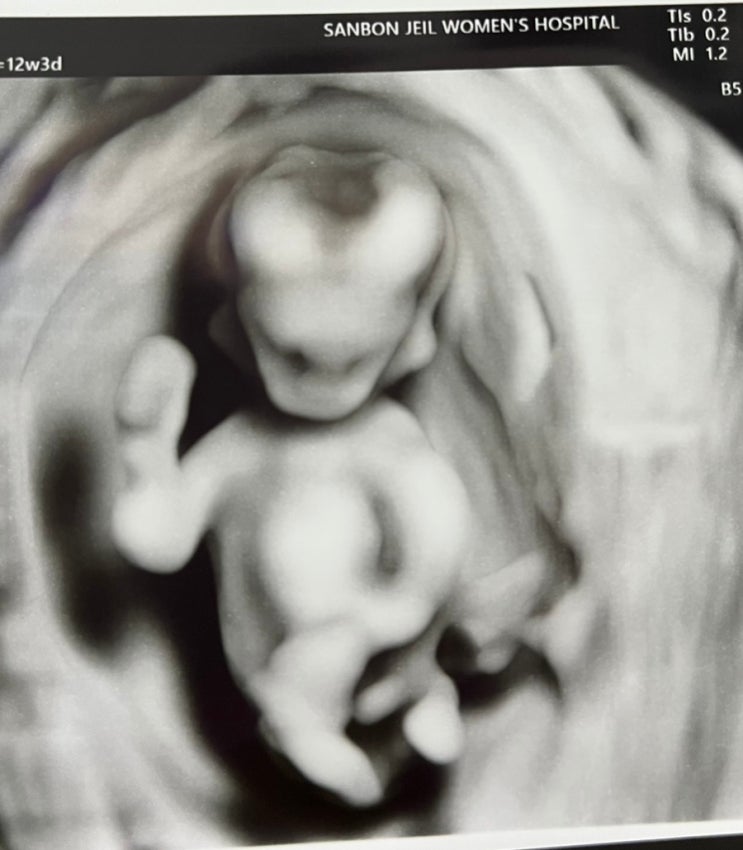

(임신초기) 임신 12주(1차 정밀초음파), 목덜미 투명대 검사, 임신 12주차 임신 증상

(임신초기) 임신 12주(1차 정밀초음파), 목덜미 투명대 검사, 임신 12주차 임신 증상 안녕하세요~ 꼬미입니...